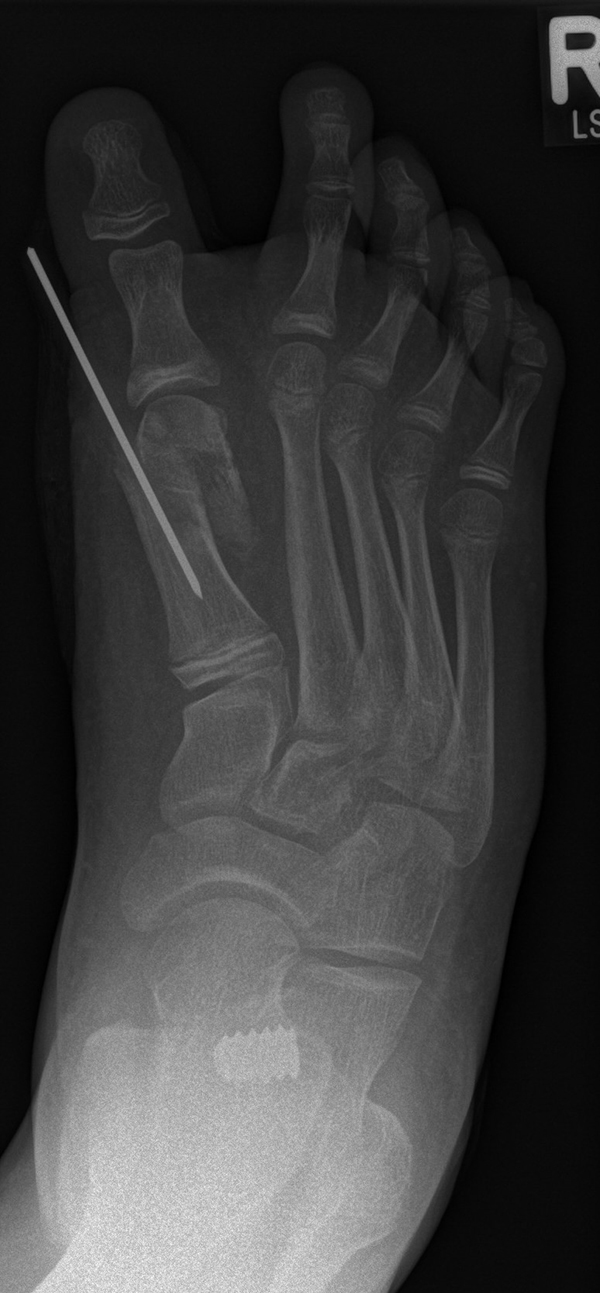

Abb. 28 a-g: Radiologischer Verlauf einer Chevronosteotomie nach dem Verfahren von M. Elkaim mit prä- (a-c drei unterschiedliche Ansichten) und intraoperativen Röntgenbildern in zwei Ansichten (d-e) sowie postoperativ zwei Ansichten (f-g).

Die Chevron Osteotomie 1 ist ohne Komplikationen am wachsenden Skelett durchführbar. Das Metatarsale I besitzt distal keine Wachstumsfuge, die geschädigt werden könnte. Die „französische Methode nach Marc Elkaim“ eignet sich für Kinder ganz besonders (Abb. 28).

Sie wird über eine eigene Tapetechnik fixiert und kann bei einem erhöhten Intermetatarsale-Winkel alternativ zur Scarf-Osteotomie durchgeführt werden. Nachteile der Methode sind eine deutliche Verkürzung durch die Fräse sowie eine starke Plantarisierung des Metatarsale I Köpfchens. Um die Verkürzung zu vermeiden, wird verlängernd in Richtung des Metatarsale II Köpfchens (nicht wie offen in Richtung Metatarsale IV Köpfchen) osteotomiert. Gleiches gilt für die starke Plantarisierung, die durch den Knochenverlust der Fräse entsteht. Die Korrektur eines kindlichen oder jugendlichen Hallux valgus ist mit der Methode ansonsten suffizient durchführbar. Wird verkürzt, muss ausreichend plantarisiert werden, um eine Transfer-Destabilisierung MT II-IV zu vermeiden.

Die MICA-Technik sollte bei geschlossenen Fugen mit einem weitem intermetatarsale Winkel durchgeführt werden. Die dafür typische Verschraubung der Osteotomie kann bei geschlossenen Fugen ohne Probleme erfolgen. Diese Osteotomie kann gut mit einer Akin- und den beschriebenen Kleinzehen-Osteotomien kombiniert werden.